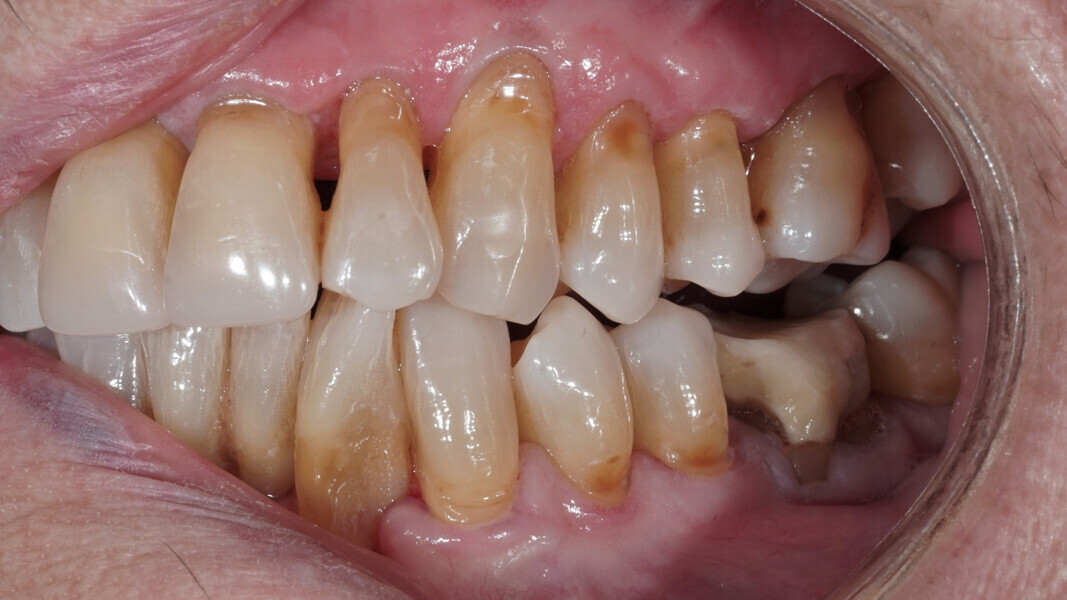

Fig. 2: Clinical situation at the initial appointment in the dental practice.

Fig. 3: Open bite in the mandibular left posterior region.